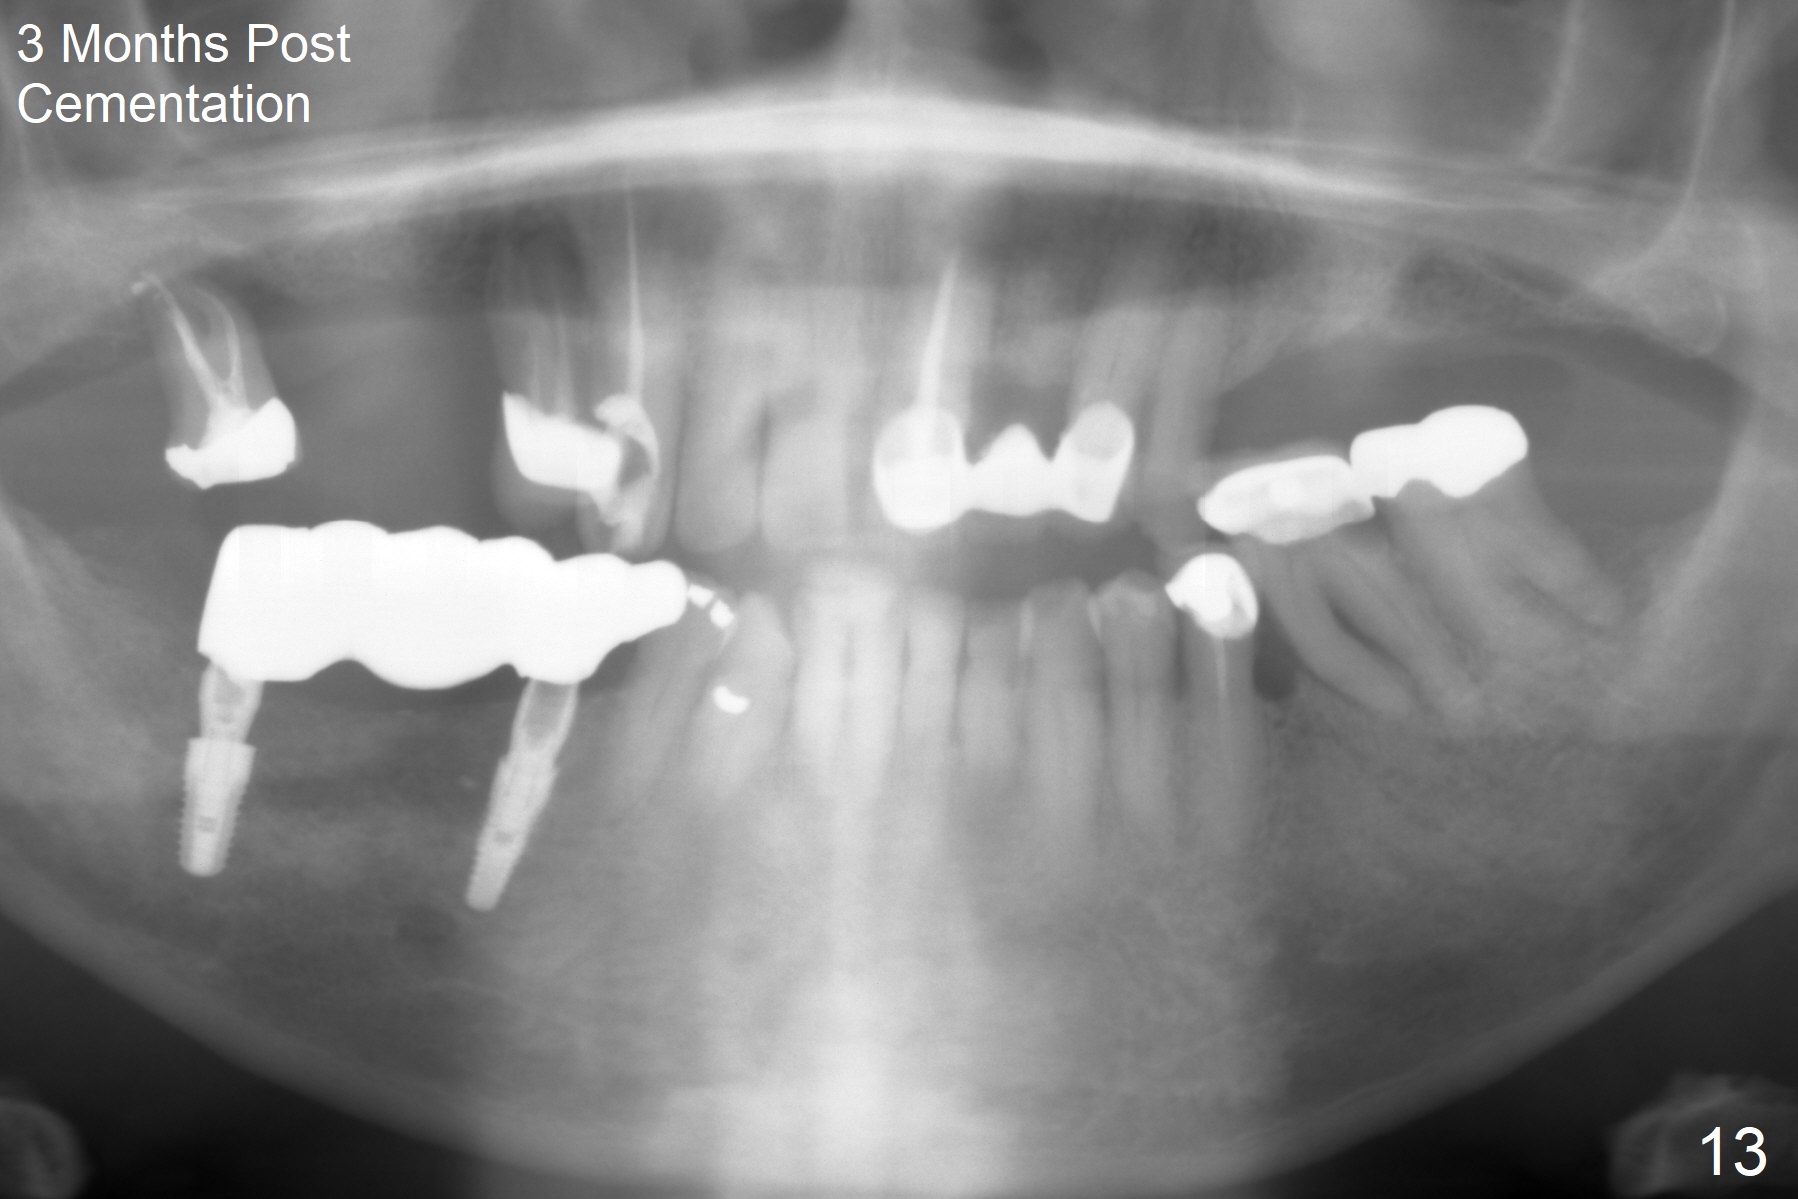

The patient will return in two weeks (total 2 months postop). The abutment at #29 will be changed to a longer one (3.9x7(6) mm). Provisional FPD will be fabricated with an emphasis to push the surrounding (especially lingual) gingiva away from the abutments, most likely using gauze as gingival retraction cord. The crown at #2 will be trimmed to have clearance. Fig.13 is taken 3 months post cementation. CBCT taken 1 year 9 months post cementation shows the uneven buccal (B) and lingual crests (Fig.14,15 arrowheads).